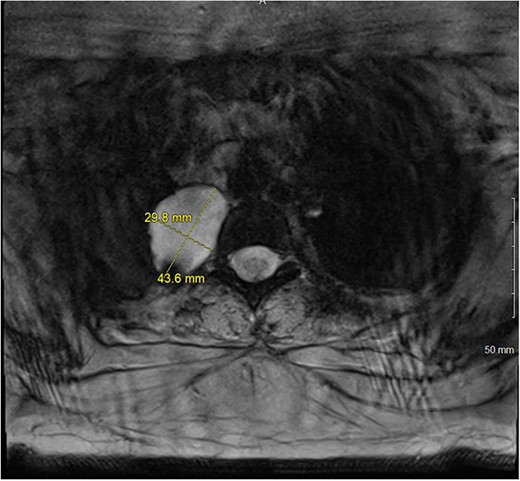

A 36-year-old female presented to an outside emergency department reporting chest pain, dizziness and abdominal pain for 7 hours. A computed tomography (CT) angiogram of the chest revealed a right paraspinal 4.2 × 2.8 × 3.3-cm cystic mass at the level of T2-3, which was well-circumscribed (Figs 1 and 2).

CT chest with IV contrast coronal view of right T2-T3 paravertebral mass.